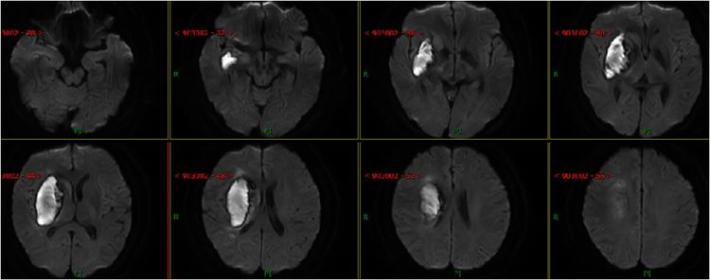

入院急查血未见明显异常指标,急查头部MRI+MRA:右侧半卵圆中心、右侧侧脑室旁多发急性脑梗死,右侧大脑中动脉重度狭窄,分枝稀疏。

分析该患者:影像学提示右侧大脑中动脉闭塞,不断进展的发病过程,提示发病机制为低灌注,确切地说是在动脉粥样硬化慢性狭窄基础上的急性闭塞,TOAST分型考虑大动脉闭塞型。药物治疗已经没有太积极的办法,患者有不断加重趋势,家属很焦急,血管内治疗能否作为最后一根救命稻草,力挽狂澜?

术后8天复查头部MRI